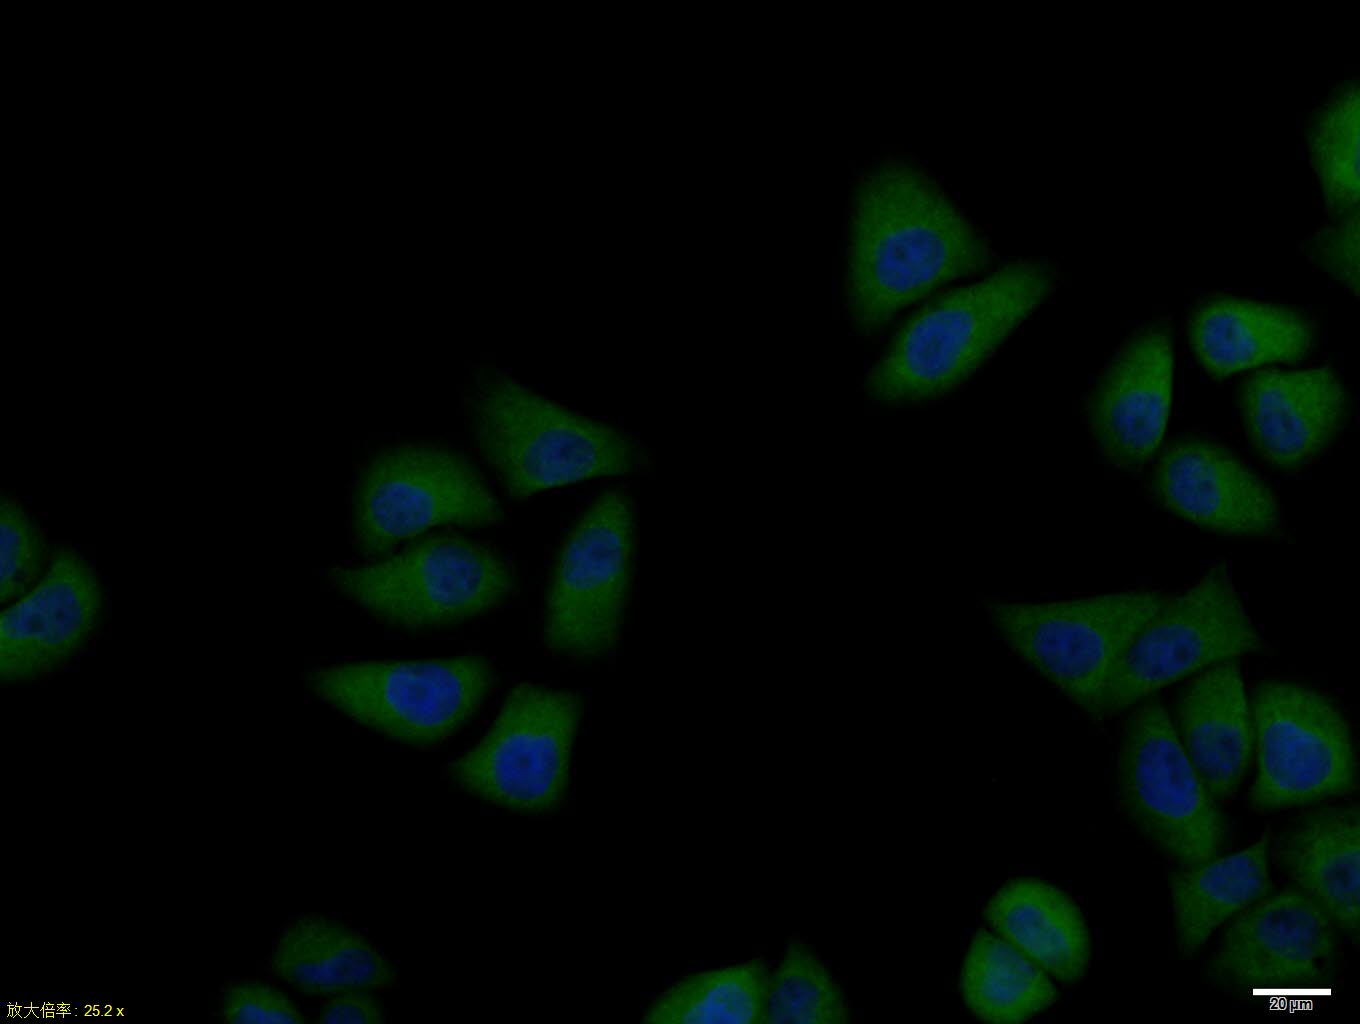

Primary Antibody (green line): Rabbit Anti-PTP1B antibody (bs-0182R)

Dilution:1ug/Test;

Secondary Antibody(white blue line): Goat anti-rabbit IgG-AF488

Dilution: 0.5ug/Test.

Isotype control(orange line): Normal Rabbit IgG

Protocol

The cells were fixed with 4% PFA (10min at room temperature)and then permeabilized with 90% ice-cold methanol for 20 min at -20℃, The cells were then incubated in 5%BSA to block non-specific protein-protein interactions for 30 min at room temperature .Cells stained with Primary Antibody for 30 min at room temperature. The secondary antibody used for 40 min at room temperature. Acquisition of 20,000 events was performed.